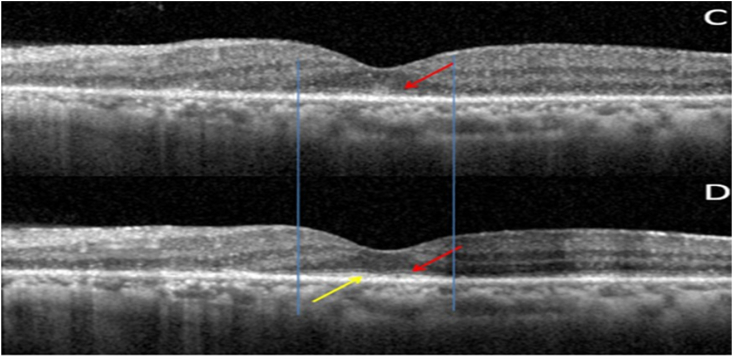

A 70 year old lady, incidentally detected to have an endometrial carcinoma Stage 3 on an executive check up, came to us with defective vision and photopsiae of both eyes of ten days duration. She was asymptomatic otherwise and thus had not taken any treatment for her gynaecological condition. Initial visual acuity was 20/80 (distance),20/200 (near) in both eyes. Pupils were sluggish binocularly; however there was no relative afferent pupillary defect. Colour vision was impaired (0/21 both eyes). Fundus was unremarkable except retinal pigment epithelium mottling at the macula.(Figure-1). Visual fields were severely depressed in both eyes (Fig. 2, Fig. 3). Magnetic Resonance Imaging (MRI)of the Brain & Orbits were normal; with no evidence of metastasis. All investigations including laboratory tests for posterior uveitis and vasculitis were done and were negative. Visual acuity worsened to Counting fingers close to face both eyes the next day. Fundus Auto Fluorescence (FAF) showed patchy hyperautofluorescence in both eyes (Figure-4). OCT Macula showed diffuse loss of ellipsoid zone (EZ), external limiting membrane (ELM), outer nuclear and plexiform layers in both eyes, except subfoveally; where EZ and ELM were faintly visible (Fig. 6, Fig. 7). Visually Evoked Potentials (VEP) both eyes showed poor waves with normal P2 latency. Electroretinography (ERG) both eyes revealed flat scotopic and photopic responses (Fig. 8, Fig. 9). Intravenous methylprednisolone 1g for 5 days was administered followed by oral steroids. Vision improved to 20/25 (distance),20/40 (near) in right eye and 20/40 (distance), 20/40 (near)in left eye respectively. Diagnosis of Cancer Associated Retinopathy (CAR) was confirmed by detection of Antirecoverin antibody (Athena Diagnostics, MA 01752,USA). Patient underwent Endometrial carcinoma surgery (Staging laparotomy with Total hysterectomy + Bilateral Salpingo-oopherectomy + removal of tumour with pelvic and para-aortic lymphnodes), radiotherapy and chemotherapy and is currently on maintenance dose of oral steroids. FAF on follow up (after 6 weeks of systemic steroid therapy) showed diffuse area of hypoautoflourescene; indicating the area of damaged retinal pigment epithelium about 1disc diameter beyond the arcades in both eyes (Figure-5). Follow up OCT of macula showed clear reappearance of ellipsoid zone (EZ) and external limiting membrane (ELM) subfoveally, where it was faintly visible previously; explaining the improvement in vision.(Fig. 6, Fig. 7); however there was no evidence of ellipsoid zone (EZ)and external limiting membrane (ELM) in the areas deficient pre-treatment. Correlating the macular hypoautoflurescence on FAF at follow up with macular OCT, we found persistent diffuse loss of outer retinal layers (ellipsoid, ELM, ONL, OPL) in both eyes. The ONL and OPL loss was more significant temporally than nasally, probably emphasising the need for careful examination of temporal retina to detect early outer retinal involvement. ERG responses continued to be grossly reduced in both eyes even after visual recovery.

Fig. 6.

(A): OD OCT Macula pre treatment showing diffuse loss of outer retinal layers (ellipsoid,ELM,ONL,OPL); more temporally. Sub-foveally faint ELM (red arrow)with isoreflectivity (yellow arrow) between ELM & RPE. (B): OD OCT Macula post treatment showing persistent diffuse loss of outer retinal layers. Sub-foveally faint ELM +(red arrow) with reappearance/reorganised ellipsoid layer (yellow arrow). Vertical blue lines depict the reappearance/reorganisation of EZ in the areas were ELM was present pre-treatment. (For interpretation of the references to colour in this figure legend, the reader is referred to the Web version of this article.)

Fig. 7.

(C): OS OCT Macula pre treatment showing diffuse loss of outer retinal layers (ellipsoid, ELM,ONL, OPL). ONL and OPL intact nasally. Subfoveally faint ELM present (red arrow). 7(D): OS OCT Macula post treatment showing persistent diffuse loss of outer retinal layers (ellipsoid, ELM, ONL, OPL). Subfoveally faint ELM (red arrow) with reappearance/reorganised ellipsoid layer (yellow arrow) is seen. Vertical blue lines depict the reappearance/reorganisation of EZ in the areas were ELM was present pre-treatment. (For interpretation of the references to colour in this figure legend, the reader is referred to the Web version of this article.)

4. Conclusions

This report aims to highlight Cancer-associated retinopathy (CAR); a potentially blinding condition with a guarded prognosis. A high index of suspicion, flat ERG, OCT changes, absence of metastasis, and positive Antirecoverin antibody clinched the diagnosis. Early systemic steroid therapy along with surgical removal of the tumour and adjuvant radiotherapy and chemotherapy helped in visual improvement in our patient. Presence of intact ellipsoid zone (EZ) and external limiting membrane (ELM) in pre-treatment OCT was found to be a positive predictor of visual recovery.